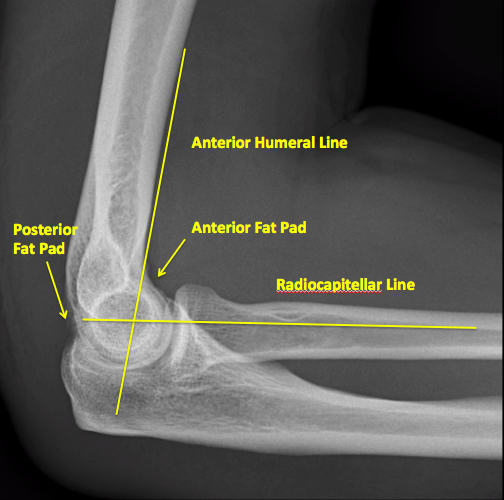

Interpreting Elbow and Forearm Radiographs — Taming the SRU

Interpreting Elbow and Forearm Radiographs — Taming the SRU Elbow Radius Bone Fracture A fracture heals between 3 to 6 weeks after the injury. Radial head fractures are the most common type of elbow fractures in adults. This can happen as a result of trauma such as a. Elbow (radial head) or neck fracture. The radius is one of the bones in your forearm. A radial head fracture happens in around 20% of. Elbow Radius Bone Fracture.